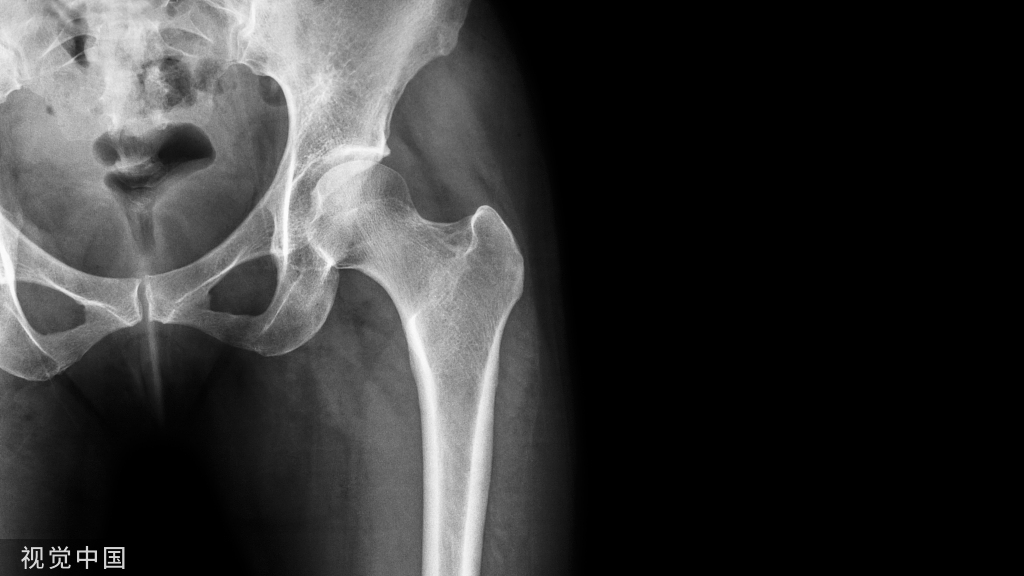

X线检查示骨纤维异常增殖症(Fibrous dysplasia ,FD)病变位于髓腔内,多见于骨干,病变区域多透亮,很少情况下出现高密度影(基质钙沉积时可出现),正常的骨小梁结构消失,代之以细颗粒“毛玻璃”样,有时病变周围的硬化骨带则可组成“果皮征”(rind sign)。